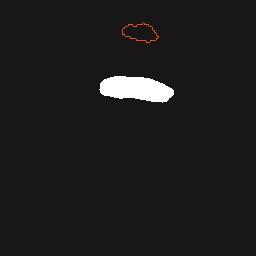

乳腺癌是全球女性最常见的恶性肿瘤之一,准确的病变分割对于乳腺癌的早期诊断与治疗具有重要意义。然而,由于病变形态的多样性以及超声成像机制的复杂性,现有基于深度学习的乳腺超声图像病变分割方法在分割准确性方面仍面临巨大挑战。为进一步提升乳腺超声图像中病变区域的分割精度,该文基于经典U-Net架构,提出了一种新型乳腺超声图像病变分割网络(CWSASKM-BBAM-Net)。首先,在网络中引入逐通道空间自适应选择核卷积模块(CWSASKM),根据不同通道的语义特征为每个空间位置自适应选择感受野大小,以增强多尺度信息的建模能力;然后,引入双向边界感知机制(BBAM),通过融合正向与反向注意力,对目标显著区域及其边界进行协同建模,同时逐步提升对非显著区域与病变区域的区分能力,以进一步强化边界信息的表达;最后,在3组公开乳腺超声图像数据集(BUSI、UDIAT和STU)上开展分割实验。结果表明:该方法在数据集BUSI上的杰卡德指数、精确率、召回率和Dice相似系数分别为71.97%、82.85%、81.40%和80.44%,较次优方法分别提升1.69、1.05、1.28和1.84个百分点;在数据集UDIAT上,这4项指标分别达到78.14%、88.31%、86.73%和86.10%,较次优方法分别提升了2.75、2.04、0.56和2.01个百分点;在外部数据集STU上,该方法也取得了优于其他方法的整体表现。实验结果表明,CWSASKM-BBAM-Net在乳腺超声图像分割任务中展现出更优的整体性能。